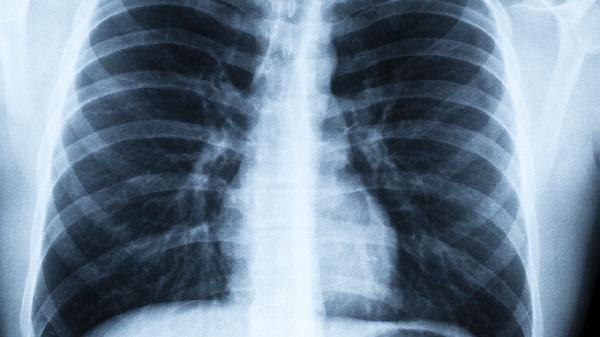

大容量全肺灌洗术通过生理盐水冲洗支气管肺泡,可清除部分粉尘和炎性物质。对于尘肺病早期患者,肺功能损伤较轻时,洗肺能显著改善咳嗽、胸闷症状,延缓肺纤维化进展。部分患者术后肺活量提升,活动耐力增强。但该操作需全身麻醉,术中可能出现支气管痉挛、灌洗液外渗等情况。术后常见一过性发热、肺部感染,多数经抗感染治疗可恢复。

尘肺病三期患者肺组织已广泛纤维化,洗肺难以逆转结构性病变。此时灌洗主要针对合并感染的痰液引流,对改善肺功能帮助有限。严重心肺功能不全者更易发生术中低血压、急性肺水肿等并发症。存在严重肺动脉高压或凝血功能障碍的患者,属于洗肺禁忌人群。

尘肺病患者应定期进行肺功能检查和胸部CT评估。除洗肺外需配合氧疗、呼吸康复训练等综合治疗,严格避免继续接触粉尘。职业暴露人群应做好防护口罩佩戴,出现持续干咳、劳力性呼吸困难时应尽早就诊。